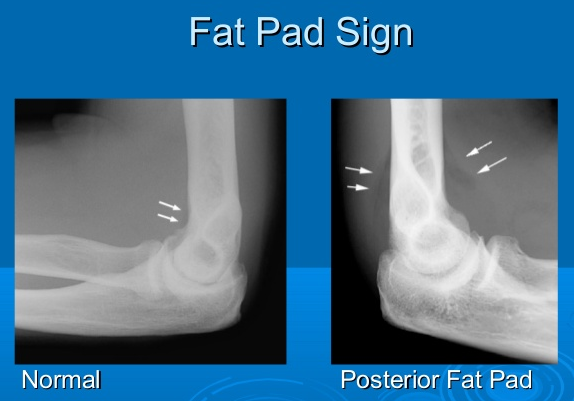

Joint effusion

abnormal fluid acculuation within the synovial compartment due to infection, inflammation or trauma

‘fat pad’ sign due to a joint effusion - observed on many abnormal elbow radiographs

extra fat deposited to help protect the bone

relevant in adults: head of radius fracture

relevant in children: supracondylar fracture

→ fat pads get pushed out, become visible on an X-ray due to swelling and displacement of fat pads → obscure the fracture visibility

sail sign

anterior fat pad, usually concealed within the coronoid fossa, becomes elevated and takes on a triangular shape

indicates joint effusion

In adults: sign of an occult fracture of the radial head

in children: supracondylar (distal humerus) fracture